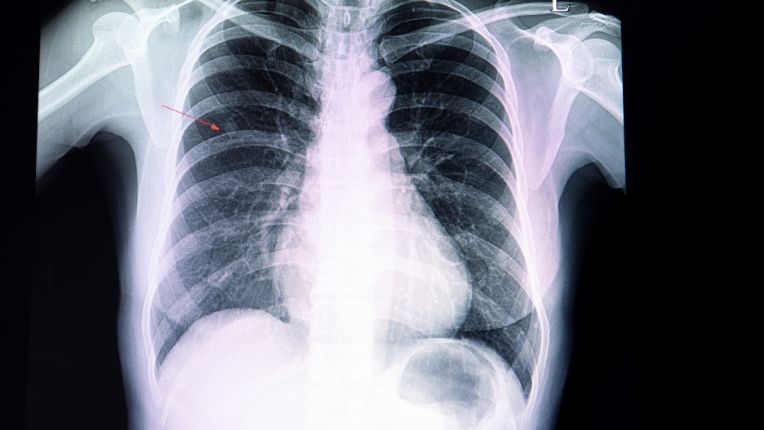

Nodule pulmonaire : Les nodules au poumon sont très fréquents. Ils peuvent être multiples et sont, dans la plupart des cas, d'une taille inférieure à 1 cm. Ils sont généralement le résultat d'une cicatrisation des poumons suite à une infection. Les inflammations chroniques peuvent aussi produire des nodules.

On peut vivre avec des nodules aux poumons. Beaucoup de patients ou patientes présentent des nodules aux poumons lorsque l'on réalise une radiographie. Bien que généralement bénins, ces nodules ne seront pas pris à la légère par l'équipe médicale qui vérifiera qu'ils sont bien inoffensifs. S'ils présentent une gêne ou sont le signe d'un cancer, une stratégie thérapeutique sera proposée aux malades.